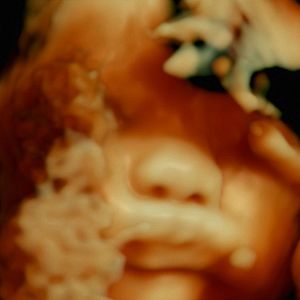

Filmado em cinco hospitais franceses nos bairros do norte de Paris, ao longo de vários anos com uma câmera especialmente projetada, este documentário revela que a carne humana é uma paisagem extraordinária que existe apenas através do olhar e da atenção dos outros.